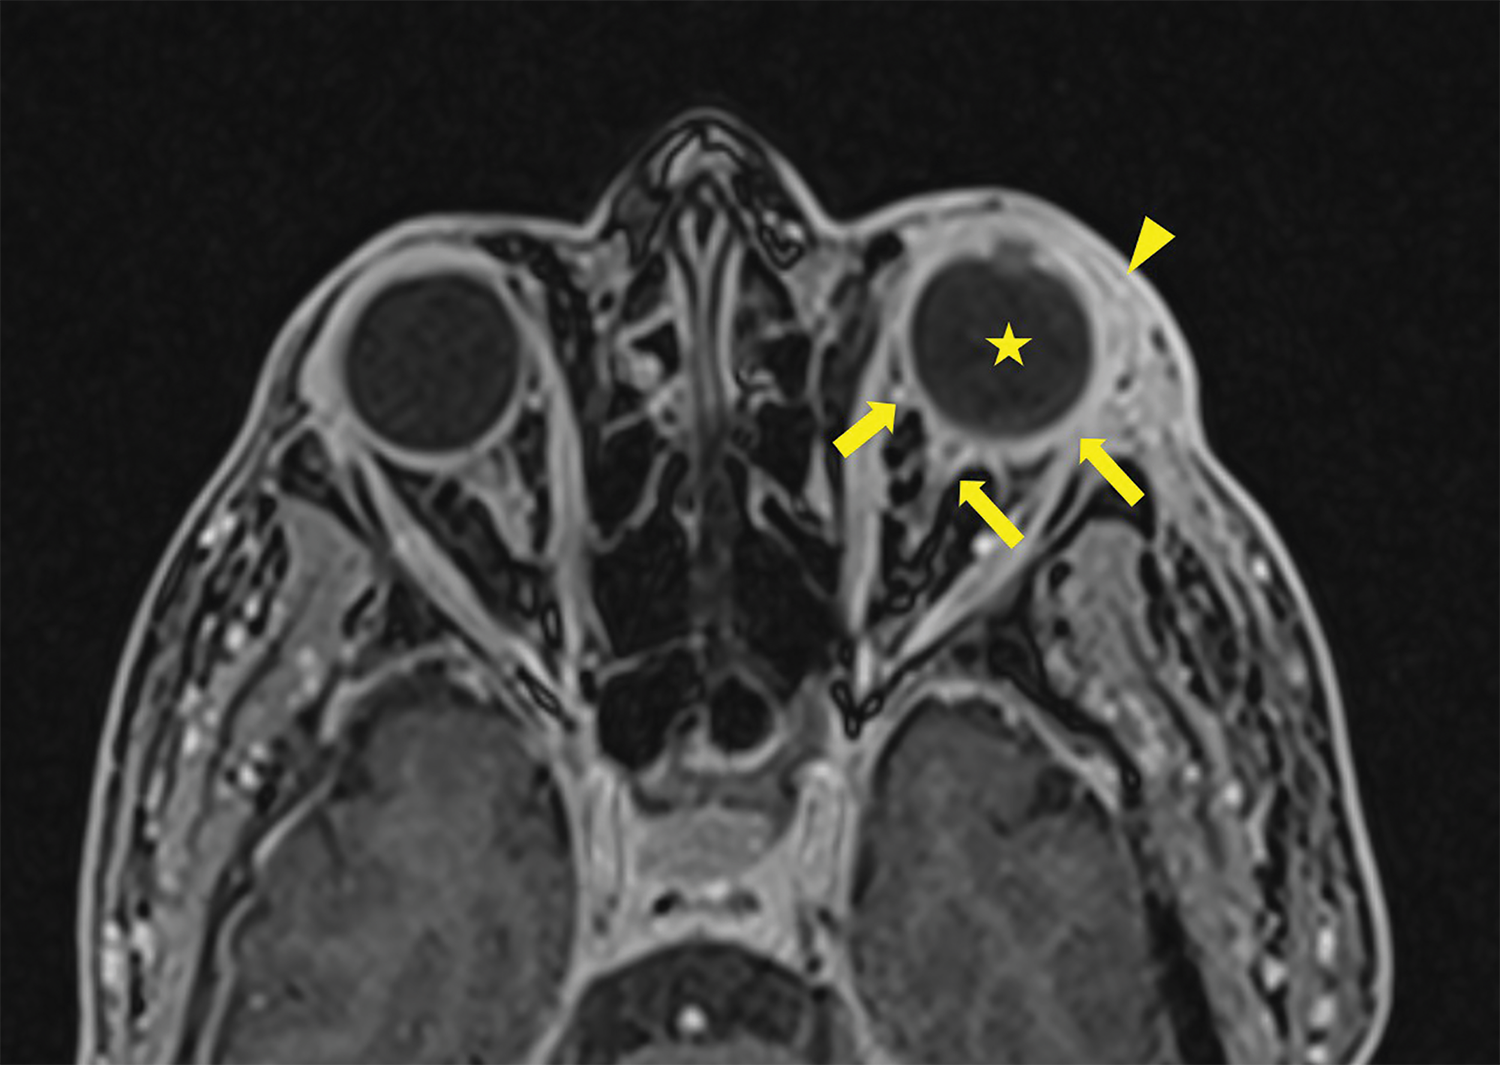

After ruling out cavernous sinus thrombosis with a contrast‑enhanced CT scan, a brain MRI was performed, confirming the diagnosis of endophthalmitis. MRI showed pre‑septal orbital cellulitis, with pre‑septal enhancement seen on the 3D T1 Dixon sequence (Figure 1, arrowhead). This was associated with increased scleral enhancement and alterations at the junction between the left ocular globe and the optic nerve (Figure 1, arrow). Of note also the slight increase in T1 signal of the vitreous body (Figure 1, star). There was choroidal and peri‑septal inflammation with fat saturation after contrast injection, and in the 3D FLAIR sequence, showing a pre‑septal and peri‑optic hypersignal (Figure 2, arrowheads). Additionally, there was an increased signal in the choroid and ciliary body, as well as thickened dura mater, in relation to the meningitis (Figure 2). Axial T2 gradient echo sequences showed retinal detachment and inflammation around the distal portion of the optic nerve, with a slight linear hypoT2 signal (Figure 3, arrow).

Figure 1

3D T1 Dixon Sequence showing pre‑septal enhancement (arrowhead) with an increase of the sclera enhancement as well as the junction between the left ocular globe and the optic nerve (arrows). Note the slight increase in T1 signal of the vitreous body (star).